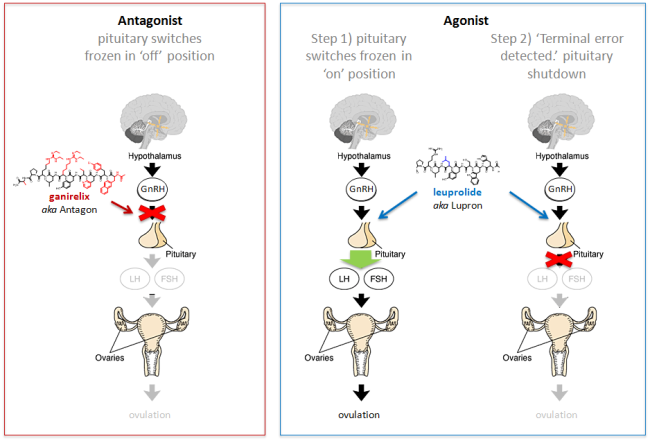

동결란 이식에서 GnRH 길항제 요법과 효능제 요법이 수정란의 상태에 어떠한 영향을 미치는가?

2013년 미국불임학회(ASRM) P-121

동결란 이식에서 GnRH 길항제 요법과 효능제 요법이 수정란의 상태에 어떠한 영향을 미치는가?